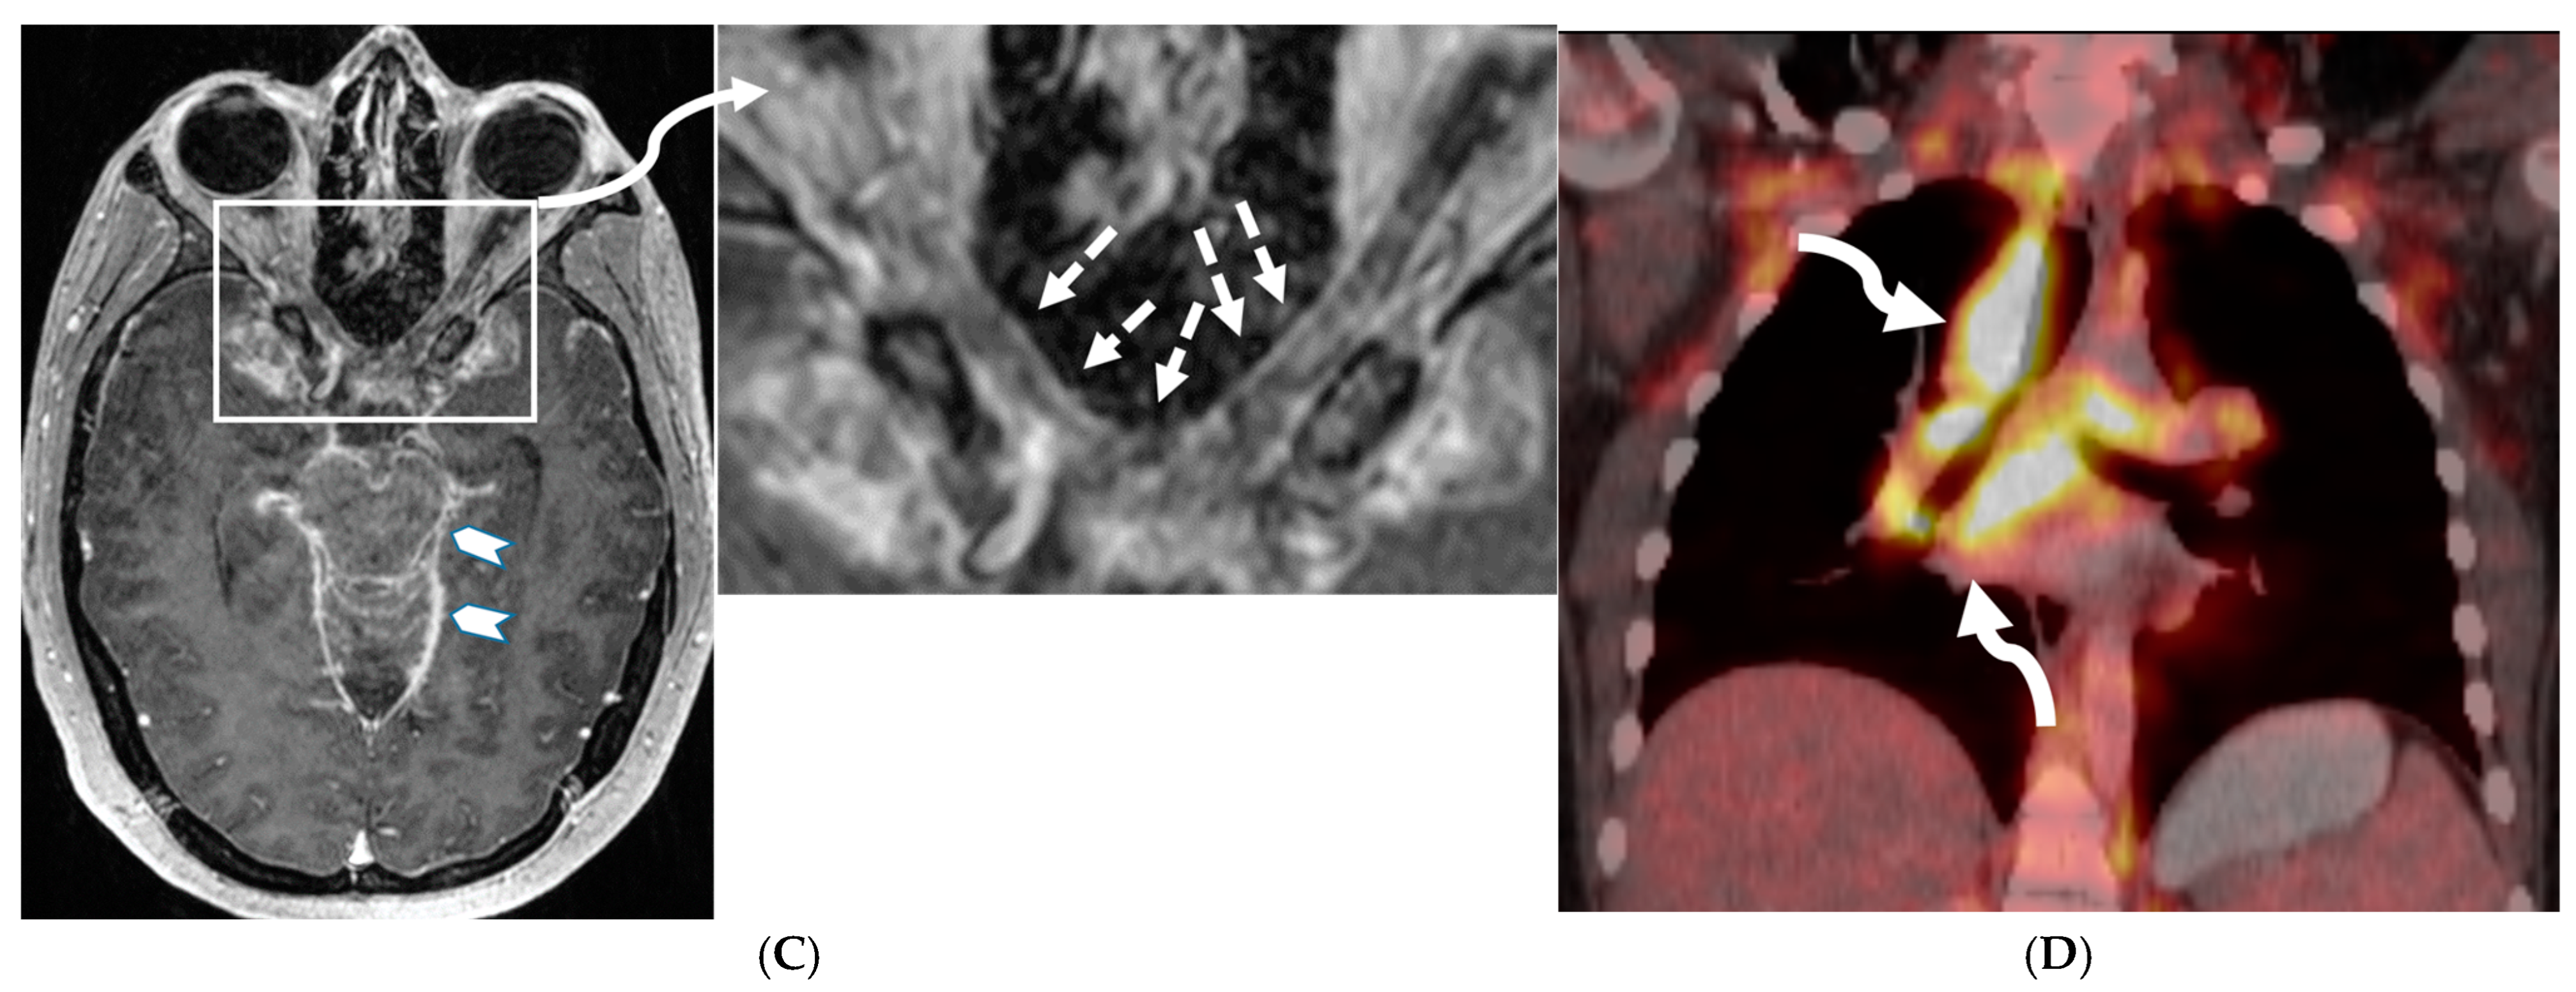

Figure 3.

18-year-old presented with headache, persistent vomiting and weight loss. History of sarcoidosis diagnosed 2 years ago. Axial Fluid Attenuated Inversion Recovery (FLAIR) (A), Axial T1 post contrast (B), Axial T1 inversion recovery post contrast (C) and Coronal Positron Emission Tomograpy (PET) scan (D): There is a heterogeneously enhancing ill-defined area of T2/FLAIR hyperintensity involving the medial aspect of the left globus pallidus (arrows), anterior aspect of the left thalamus and left hypothalamic region. Diffuse enhancement of the basal meninges, tentorium, throughout perisylvian sulci (arrow heads), along the infundibulum, and posteriorly at the craniocervical junction. There is also enhancement along optic nerve sheath (dashed arrows). Features are highly consistent with extensive neurosarcoidosis given the previous history of thoracic sarcoid. PET scan from 2 years earlier demonstrating avid uptake of radiotracer (curved arrows). Radiologically, the differential diagnosis includes tuberculosis and metastatic process. Patient made complete recovery after treatment for sarcoid.

Figure 21.

Sagittal T2 (A,B), axial FLAIR (C), axial T2 cervical spine (D) at the level of C7 vertebral body and Axial T2 orbits (E): 12-year-old girl presented with right focal motor seizure and left temporal lobe slowing on electroencephalogram (EEG). Right eye vision loss and irritability. Ill-defined areas of signal abnormalities are identified within the RIGHT mesial temporal lobe and bilateral medulla (white arrows). FLAIR hyperintensity is identified on the left central sulcus (black arrow). Small focus of signal abnormality is seen on the right side of the cord at the 7th cervical vertebra (C7) (dashed arrow). There is also bilateral papilledema (arrowheads). Post contrast axial T1 (F,G), axial T1 orbits (H) and axial T1 cervical spine at C7 (I): Asymmetric LME (black arrows) predominantly involving the left cerebral hemisphere, with minimal right parietal involvement is seen. Ill-defined enhancement in the right mesial temporal lobe, and right greater than left medulla (white arrows) corresponds to the signal abnormality. There is right greater than left, optic nerve enhancement (curved arrow). Single small enhancing lesion in the spinal cord on the right at the level of C7 corresponds to the signal abnormality (dashed arrow). Features favor a demyelinating process. MOG antibodies were positive at 1:20 in keeping with Myelin oligodendrocyte glycoprotein (MOG) antibody disease (MOGAD).